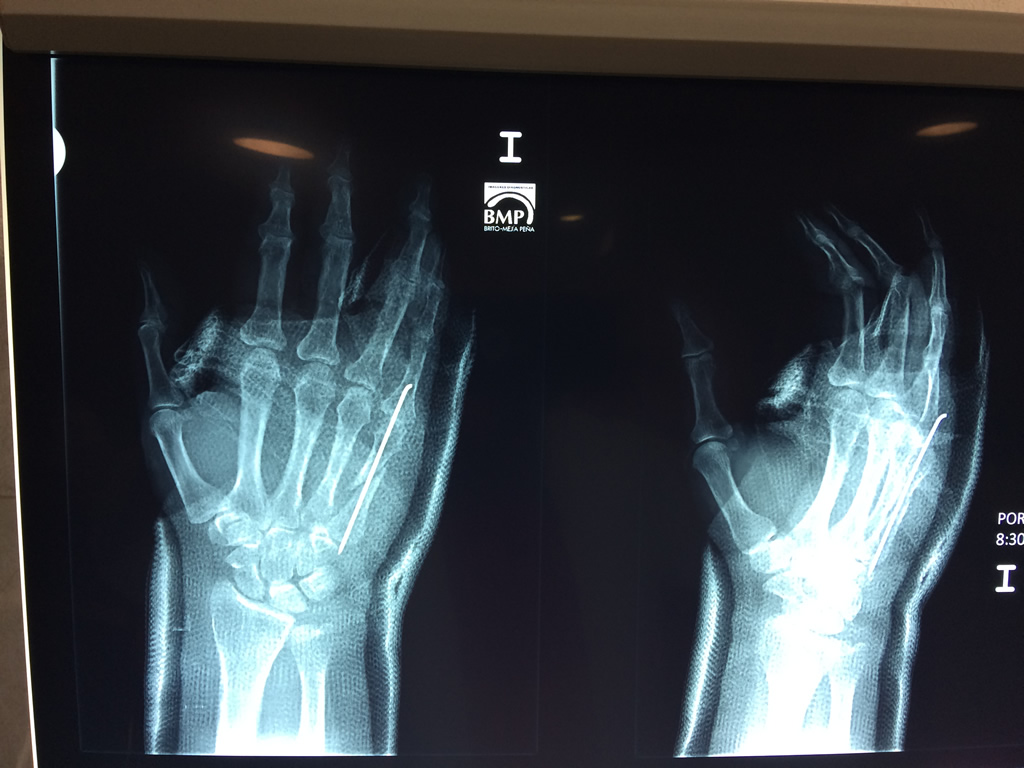

Cirugías de Calcaneo - Cirugías de Muñecas y Manos

Los procedimientos más comunes en cirugía de la mano son aquellos destinados a reparar traumatismos, incluyendo lesiones de tendones, nervios, vasos sanguíneos, y articulaciones; huesos fracturados; y quemaduras, cortes, y otros daños de la piel.